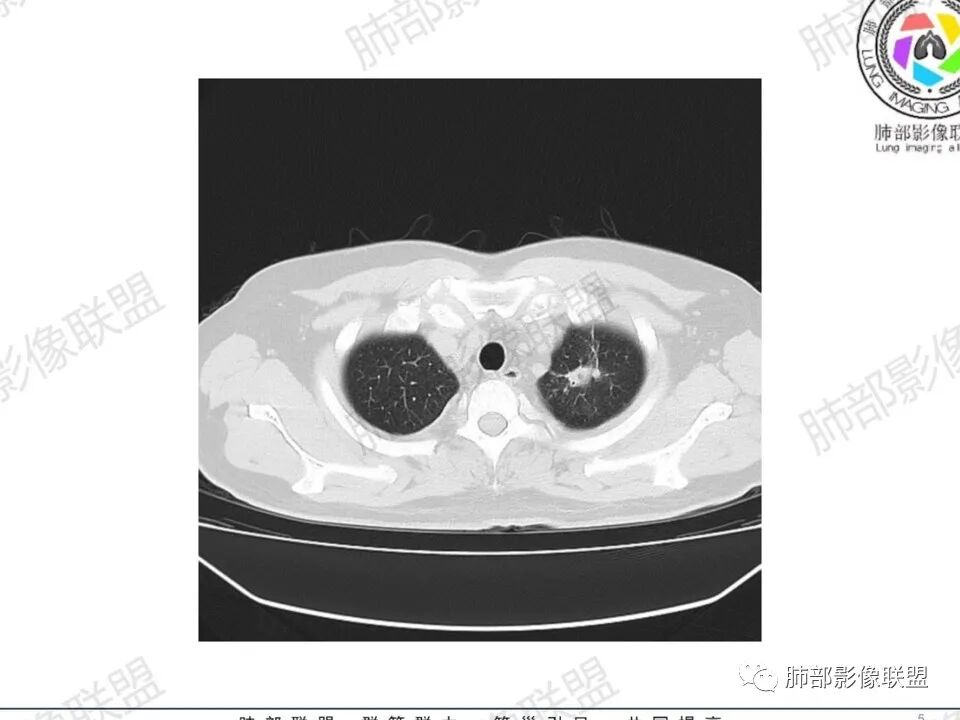

双肺多发结节,胸膜下为主,部分可见空洞。左肺上叶尖后段结节较大,分叶毛刺,周围可见长条索及小斑片影,内空洞比较光滑,内侧壁可见支气管通过。右肺下叶后基底段不张实变,后侧积液,右侧水平裂积液,右侧膈胸膜纵膈胸膜增厚积液,右侧侧胸膜肥厚,考虑1:一元金葡。2二元:金葡,左肺上叶结核。

男,45岁,左手指红肿疼痛两天,右侧胸壁疼痛伴发热12小时入院。患者急性起病,胸部CT示双肺多发结节,部分伴空洞,空洞壁较光滑,右侧胸腔积液,考虑感染性病变,金葡菌加SPE可能

中年男性,左手中指及胸壁疼痛伴发热来诊,影像见双肺多发结节,胸膜下分布为主,部分结节可见空洞,边缘模糊。左肺上叶尖后段结节较大。右肺下叶后基底段不张实变,右侧叶间裂及右侧胸腔积液,右侧侧胸膜肥厚。考虑金葡菌感染,血播SPE。

胸膜下为主多发结节,边缘光滑

伴随楔形影,支气管壁不增厚